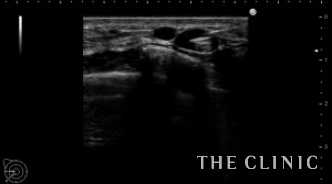

エコーでは大きなしこり以外にも小さなしこりを多数認めました。

小さなしこりも除去します。

除去後ヒアルロン酸は消失しました。

- 右

- 左

ヒアルロン酸注入によるしこりのエコー診断カルテ